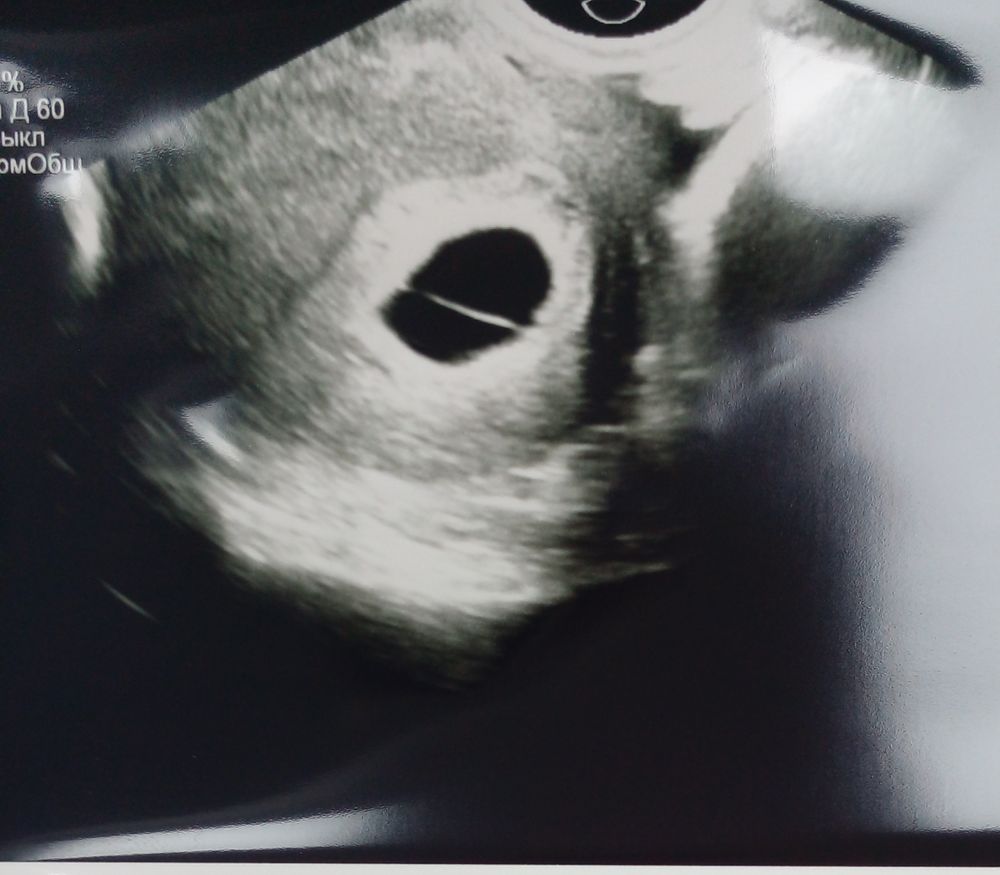

Эмбриона нет, звука сердца тоже! 7 неделя акушерская, пя 21, 2. Посоветовали пересдать через 10 дней и следить за хгч! Хгч упал. Мне не понятна нить вдоль плодного яйца? У кого так было ?

Плодное яйцо для 7 недель отличное

а остальное очень странно, даже желточного мешочка нет?

Как будто перегородка как при двойне. Попробуйте через дней 5 повторить

А там точно 1 плодное яйцо? А то кажется будто это 2 маленьких. Если по теме у меня когда ПЯ было 22мм был эмбрион 4 мм и ЖМ